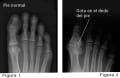

Mientras que las radiografías de las extremidades (manos y pies) a veces son útiles en las últimas etapas de la enfermedad, las radiografías no suelen ser útiles al principio en el diagnóstico. El dolor suele hacer que las persones busquen atención médica antes de que puedan verse cambios a largo plazo en una radiografía. Pero las radiografías pueden ayudar a descartar otras causas de artritis.